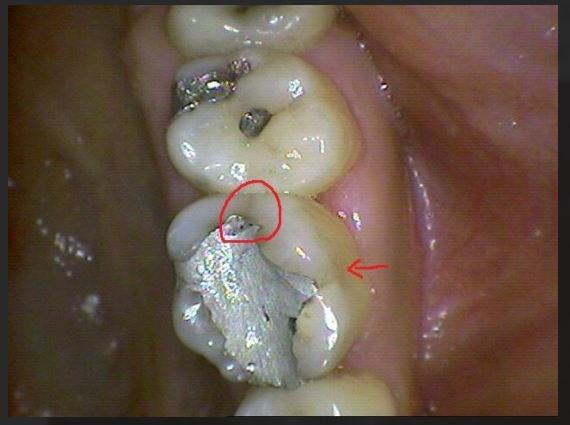

그러나 일단 증상이 나타나면 씹을 때 시큰거리는 증상이 있지만 초기엔 가만히 있을 경우엔 통증이 없다가 씹을 때 간헐적으로 통증을 느끼다 점점 지속적인 통증을 호소하게 됩니다. 씹을 때 금이 간 부분에 자극을 받으면서 그 부분이 살짝살작 벌어지며 신경을 자극하고 심할 경우 사용을 하지 않아도 통증이 계속되며 나증엔 금이 가서 벌어진게 눈에 보일경우도 있습니다.